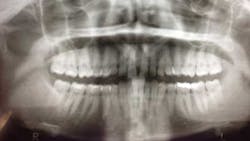

Early assessment for potential impaction is easily done by taking a panoramic radiograph at the age of 7. Ectopic positioning of canines may result in future impaction; if this is the case, then intervention can be initiated. Research has also shown that early removal of the deciduous canines can offer a favorable eruption pattern of permanent counterparts. (4,5) If crowding is present, then the arch can be expanded.

When a full permanent dentition is present (with the exception of impacted canines), the labial/palatal position of the canine will have an influence on what the provider can do. (1) Arguably, obtaining a CBCT is considered mandatory and will allow for a more inclusive treatment plan creation. If angulation is favorable, then consideration to remove the primary canine and wait six months to see if there is movement of the permanent canine is an option. If extraction of the canine(s) is needed, then a premolar substitution, which is dependent on occlusion, can be used in the space. An implant can also be an appropriate alternative. When pulling a canine into the occlusal arch, there is risk involved. Trauma to adjacent teeth (root resorption) and ankylosis are some of the most common complications.The patient was put in full orthodontics and referred to a surgeon for extraction of the primary canines, exposure, and placement of retention on the impacted canines to pull them directly down from their current position.